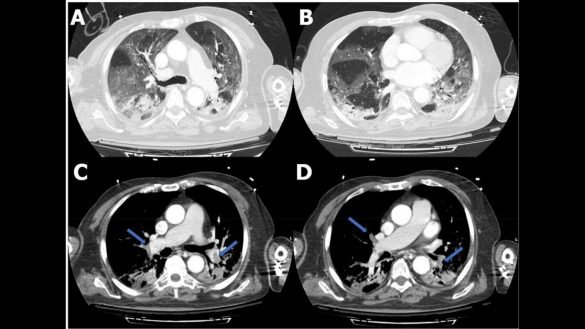

Technique systématiser l’angioscanner désormais dans tous les COVID-19 by jamel MOUHLI 29 avril 2020 written by jamel MOUHLI 29 avril 2020 0 comments 2 minutes read Bookmark 502 Maladie thromboembolique pulmonaire, cérébrale et rénale associée à une infection par COVID-19 systématiser l’angioscanner désormais dans tous les hôpitaux de France et pas seulement : « d’abord, parce qu’on sait traiter l’embolie pulmonaire à base d’anticoagulants. Et parce qu’ensuite, pour les patients Covid, ça veut dire qu’il ne restera plus que la problématique ventilatoire que les réanimateurs savent prendre en charge de façon efficace ». il faut demander un Angio scanner à base dose Les scientifiques chinois disent que le nouveau coronavirus ne sera pas éradiqué, ajoutant à un consensus croissant dans le monde entier que le pathogène reviendra probablement dans des vagues comme la grippe. Il est peu probable que le nouveau virus disparaisse comme son cousin proche SRAS l’a fait il y a 17 ans , car il infecte certaines personnes sans provoquer de symptômes évidents comme de la fièvre. Ce groupe de soi-disant porteurs asymptomatiques rend difficile la maîtrise totale de la transmission car ils peuvent propager le virus sans être détectés, a déclaré lundi à Pékin un groupe de chercheurs chinois dans le domaine de la virologie et de la médecine. une épidémie qui coexiste avec les humains depuis longtemps, devient saisonnière et se maintient dans le corps humain », a déclaré Jin Qi, directeur de l’Institut de biologie des agents pathogènes du principal institut de recherche médicale, l’Académie chinoise des sciences médicales.» on commence à comprendre cette maladie ,avec plusieurs phases, et plusieurs stades il faut traiter les patients le début , et la confrontation avec les problèmes de coagulation, des phlébites ,et même des embolies pulmonaires, La découverte de l’équipe du Professeur Eric Delabrousse au CHU de Besançon va vraisemblablement permettre de sauver davantage de vies parmi les patients Covid-19 gravement touchés au plan respiratoire. Grâce à un angioscanner pulmonaire qui révèle les embolies pulmonaires non détectées jusqu’alors. L’étude « made in CHU de Besançon » vient d’être publiée ce jeudi par la revue scientifique américaine Radiology, mondialement reconnue dans le domaine médical. Elle a été menée durant trois semaines (16 mars au 4 avril 2020) par une équipe composée des Professeurs Éric Delabrousse (chef du Pôle Imagerie), Sébastien Aubry (chef du service Radiologie) et des Docteurs Julien Behr (radiologue spécialiste du poumon), Paul Calame (praticien hospitalier), Franck Grillet (chef de clinique). Published today in @radiology_rsna: Acute Pulmonary Embolism Associated with COVID-19 Pneumonia Detected by Pulmonary CT Angiography. https://t.co/J5JGKhQiRc #COVID19 #ChestRad pic.twitter.com/D4FfynIfAV — Radiology (@radiology_rsna) April 24, 2020 COVID 19h homme 57ans thrombophlébite poplité COVID 19h homme 57ans thrombophlébite poplité https://pubs.rsna.org/doi/10.1148/radiol.2020201623 Post Views: 216 Share 0 FacebookTwitterPinterestEmail jamel MOUHLI Following Author previous post Une attention particulière doit être portée à la prophylaxie de la thromboembolie veineuse dans la p next post Donner des anticoagulants aux patients Covid-19 gravement malades gagne du terrain You may also like Bookmark L’athérectomie orbitale : un nouvel outil disponible ,la... 14 décembre 2025 Bookmark Les médecins vasculaires (angiologues), les chirurgiens vasculaires et... 3 octobre 2022 Bookmark Review of Endovenous Thermal Ablation of the Great... 20 novembre 2020 Intubation trachéale pendant la pandémie de COVID-19 9 juin 2020 Bookmark Une étude établit un lien entre embolie pulmonaire... 27 mai 2020 Bookmark The Global Embolization Symposium and Technologies (GEST) 27 novembre 2015